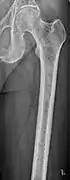

The diagnostic examination of a person with suspected multiple myeloma typically includes a skeletal survey. This is a series of X-rays of the skull, axial skeleton, and proximal long bones. Myeloma activity sometimes appears as "lytic lesions" (with local disappearance of normal bone due to resorption) or as "punched-out lesions" on the skull X-ray ("raindrop skull"). Lesions may also be sclerotic, which is seen as radiodense.[64] Overall, the radiodensity of myeloma is between −30 and 120 Hounsfield units (HU).[65] Magnetic resonance imaging is more sensitive than simple X-rays in the detection of lytic lesions, and may supersede a skeletal survey, especially when vertebral disease is suspected. Occasionally, a CT scan is performed to measure the size of soft-tissue plasmacytomas. Bone scans are typically not of any additional value in the workup of people with myeloma (no new bone formation; lytic lesions not well visualized on bone scan).

Femur with multiple myeloma lesions